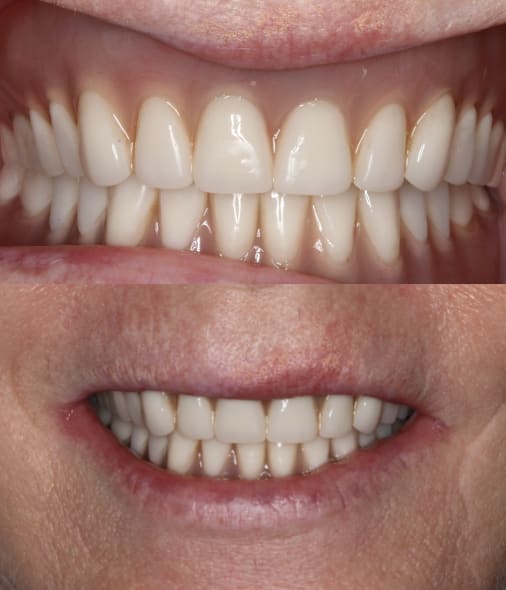

A polymethyl methacrylate (PMMA) appliance was verified for occlusion and esthetics (Figure 10). Once esthetics were evaluated and approved the final LOCATOR FIXED® prosthesis was processed in BruxZir zirconia (Glidewell). The black laboratory procession attachments were removed and replaced with the appropriate final LOCATOR FIXED® insert (Figure 11). The LOCATOR abutments and processing attachments are illustrated in Figure 12, which shows the tools for seating and removing the proprietary inserts and the insertion and removal tools. Proper inserts were selected and positioned per the manufacturer’s instructions (Figure 13). The final zirconia fixed prosthesis was seated using the seating tool and evaluated for stability (Figure 14). The prosthesis allowed for minimal palatal coverage, and the functional and esthetic maxillary reconstruction was complete (Figure 15 and Figure 16).

The patient was so pleased with the function, esthetics, and retention and the elimination of the palatal coverage that she requested a mandibular LOCATOR FIXED® restoration to replace the existing LOCATOR overdenture. Figure 17 illustrates the removal tool of this fixed prosthesis. The instrument engages under the bridge’s distal extensions for removal. Final CBCT analysis indicated acceptable integration of the dental implants supporting the fixed prosthesis (Figure 18).